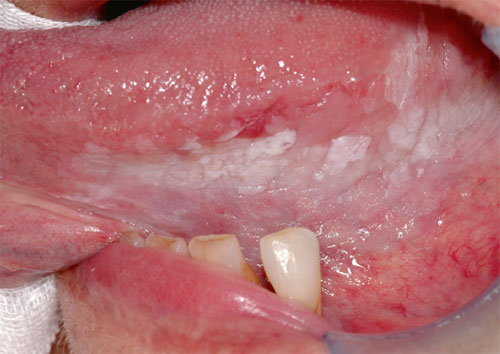

Grossflächige Leukoplakie am linken Zungenrand mit Ausdehnung auf den Mundboden.